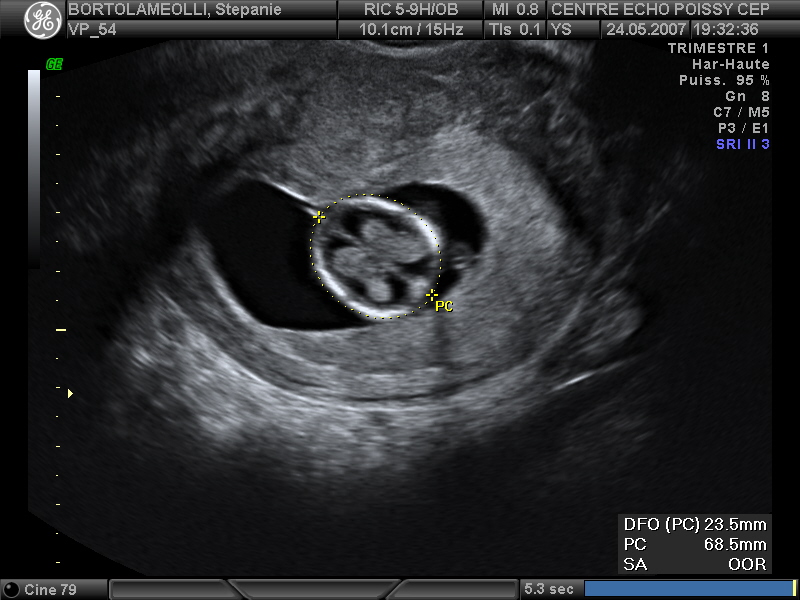

Echographies

Mai 2007